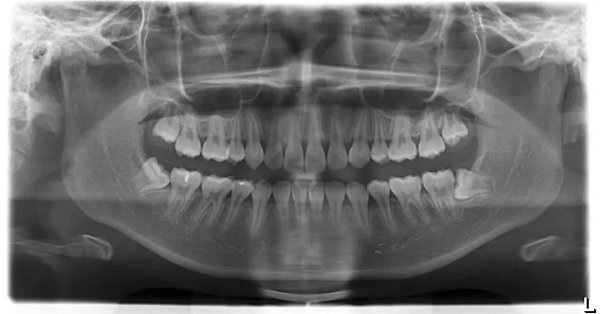

1.牙全景片:全口牙齿、牙周、及相邻的结构的情况;